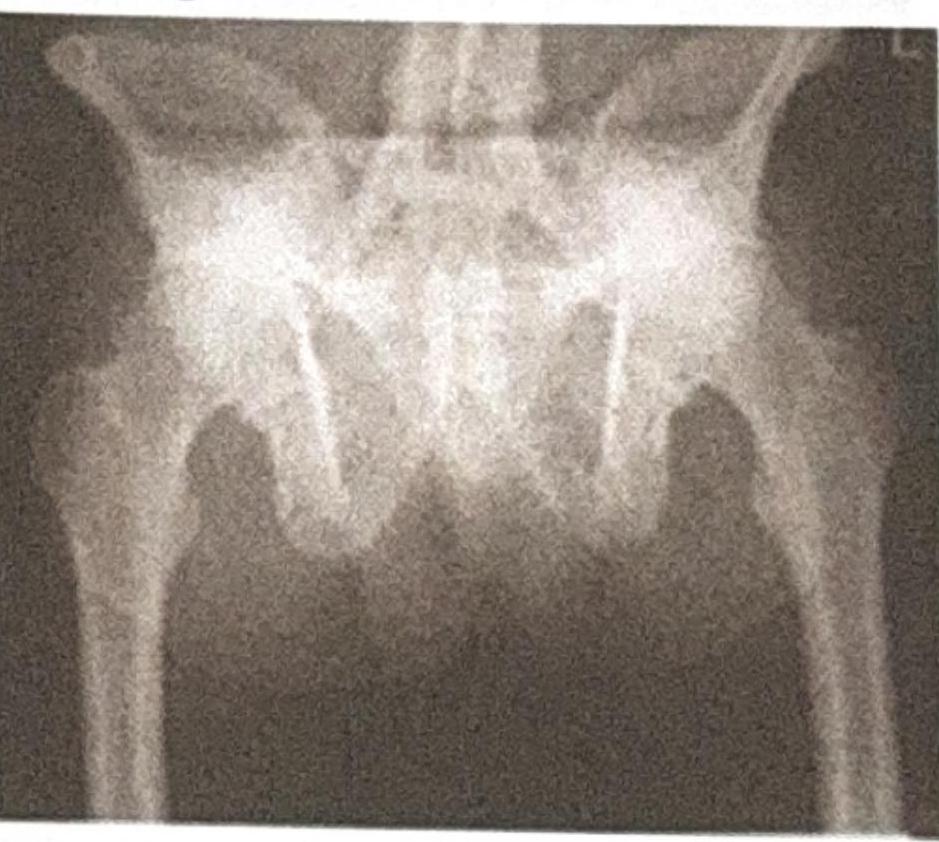

A 50-year-old male presents with backache, morning stiffness, red eye, and ankle swelling. Based on the X-ray provided, what is the most likely diagnosis?

Explanation: ***Ankylosing Spondylitis*** - The X-ray likely shows features of **sacroiliitis** (joint space narrowing, sclerosis, erosion) and possibly **vertebral fusion**, consistent with ankylosing spondylitis. The clinical presentation of **backache, morning stiffness, red eye (uveitis), and ankle swelling (enthesitis)** are classic extra-articular manifestations and peripheral arthritis of ankylosing spondylitis. - X-ray findings like **bamboo spine** (late stage), syndesmophytes, and erosions of the sacroiliac joints are characteristic of this seronegative spondyloarthropathy. *Paget's Disease* - Paget's disease is characterized by disorganized bone remodeling, leading to bone enlargement, deformity, and increased density or lysis. It typically does not present with **sacroiliitis** or widespread **ankylosis**. - Clinical features usually include **bone pain**, **bone deformities**, and potentially **nerve compression**, which are not the primary symptoms described. *Healed TB spine* - Healed TB spine (Pott's disease) would typically show bone destruction, collapse of vertebral bodies, **kyphosis**, and often calcified abscesses. - While backache can occur, the presence of **red eye** and **ankle swelling** are not characteristic of spinal tuberculosis. *Osteopetrosis* - Osteopetrosis is a rare genetic disorder characterized by **increased bone density** due to defective osteoclast function, leading to abnormally thick and brittle bones. - The X-ray would show **generalized sclerosis** (diffuse increased bone density) throughout the skeleton, which is not the primary finding indicated by the clinical context of sacroiliitis and joint fusion.